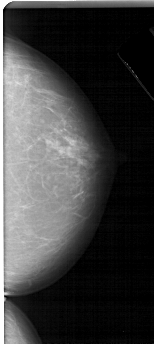

A_1694_1.LEFT_CC

LEFT_CC LINES 5356 PIXELS_PER_LINE 2431 BITS_PER_PIXEL 12 RESOLUTION 43.5 NON_OVERLAY